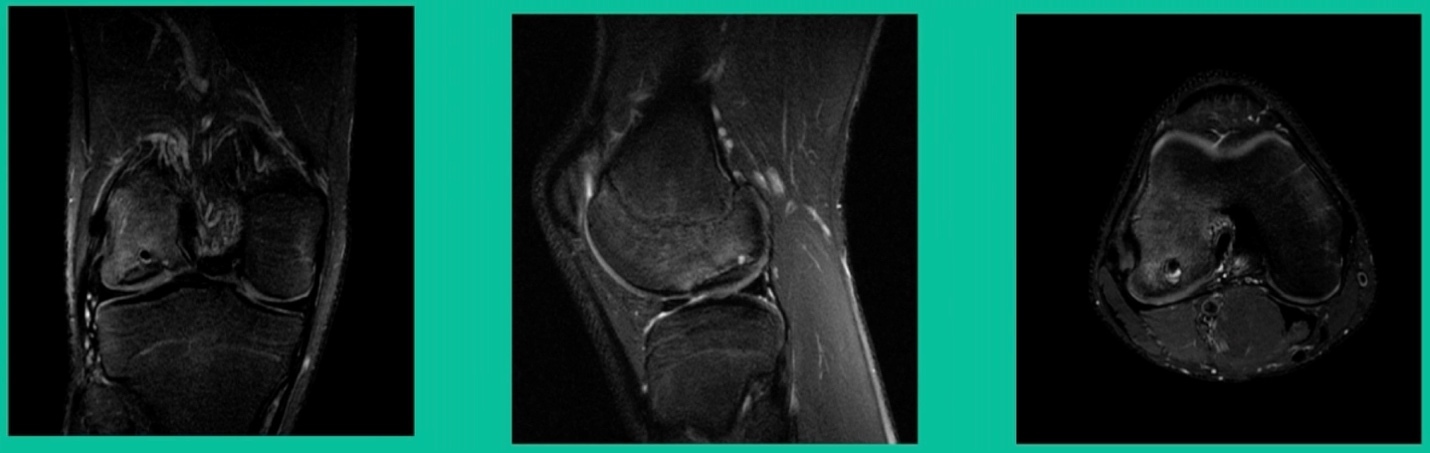

Another case example. 14-year-old male tennis player, 10 months of knee pain (Figure 7A).

This is a Trochlear defect (Figure 7B).

This goes back to metallic screw fixation, because this one is macroscopically unstable. That is a fracture non-union. That’s an atrophic non-union. Debride it, curette it, drill it, and thenwe use metal screws because it’s macroscopically unstable.

However, in this instance, we did take the screws out.

He was back to everything at 16 weeks and, at two years, he had no further symptoms. How do these do? There’s plenty of literature that shows that metallic screw fixation for unstable OCD, not just in juveniles, but in adults, will lead to reliable fixation. It’s a four-month process. They get back to everything, and they rarely have problems downstream.